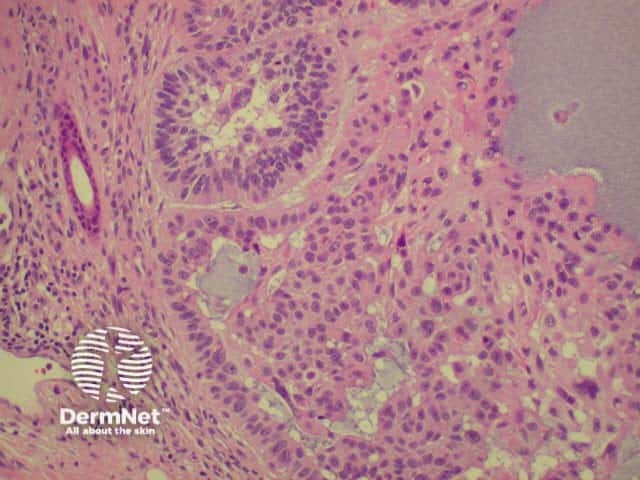

Histology of basal cell carcinoma